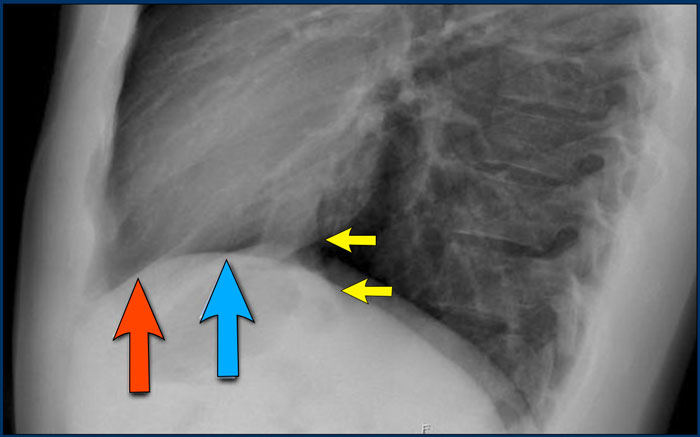

Diaphragm Evaluation

• The right hemidiaphragm should be clearly visible anteriorly up to the chest wall (red arrow), representing the interface between aerated lung and abdominal soft tissues.

• The left hemidiaphragm is usually visible only up to the point where it is adjacent to the cardiac silhouette (blue arrow), beyond which the interface is lost due to the similar radiodensity of the heart and upper abdominal contents.